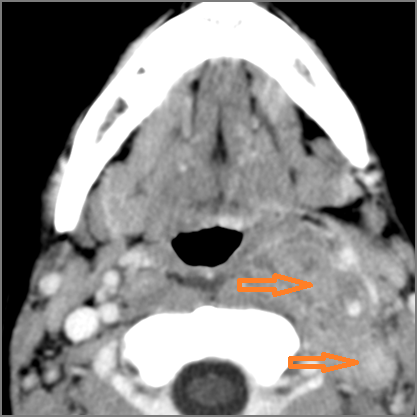

9 month old male presenting to the emergency room with poor feeding, fever, respiratory distress and possible retropharyngeal abscess or suppurative retropharyngeal adenitis.Exam

There is excessive enhancement or thickening of the mucosa or hypertrophy of the palatine or lingual tonsillar tissue or the lymphoid tissue along the glossotonsillar sulci and posterior pharyngeal wall. |

Yes | NA |

There is reactive retropharyngeal lymphadenopathy. |

There is suppurative retropharyngeal lymphadenopathy. |

If there is suppurative retropharyngeal adenopathy what is the maximum short axis dimension of the largest suppurative node. Measurement |

< 2cm | NA |

Pharyngitis with suppurative retropharyngeal adenitis.